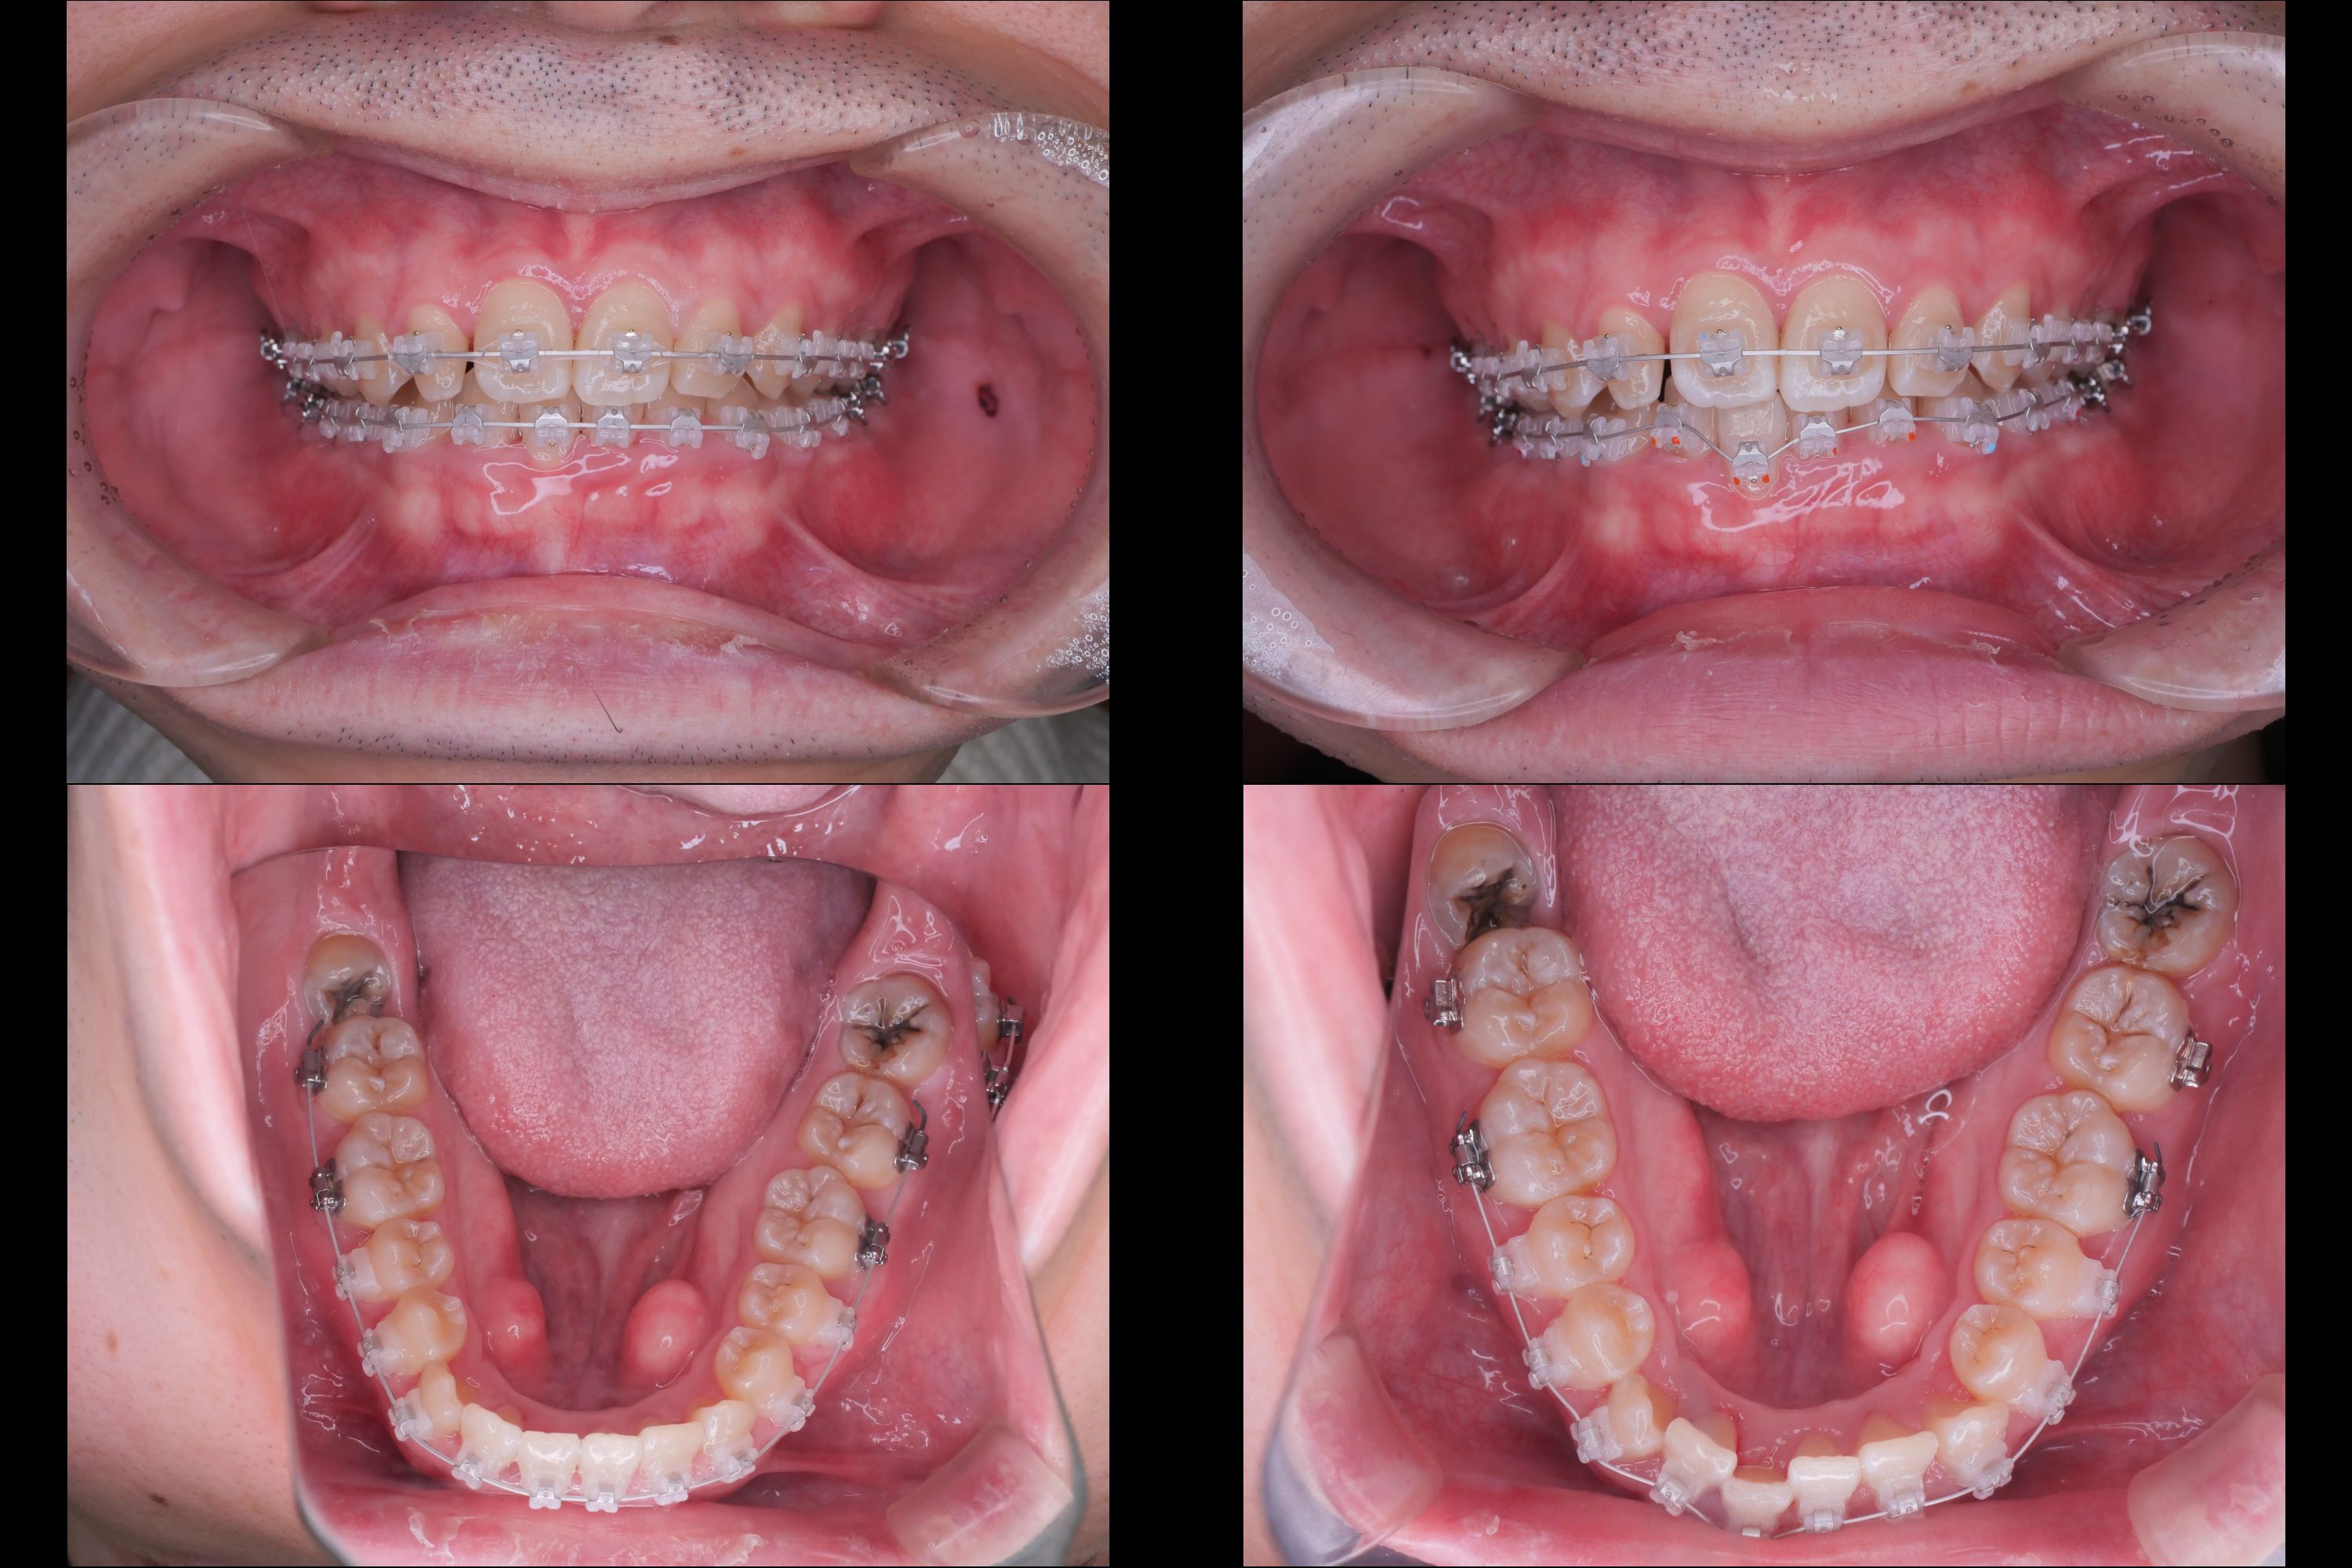

名古屋市中区錦3丁目にある栄駅前矯正歯科クリニックが、矯正歯科治療を専門に行う歯科医院として、矯正治療についてのさまざまな情報を発信します。興味深い情報や、お口まわりをきれいに役立つ情報をお伝えしますので、ときどき目を通していただけると嬉しいです。